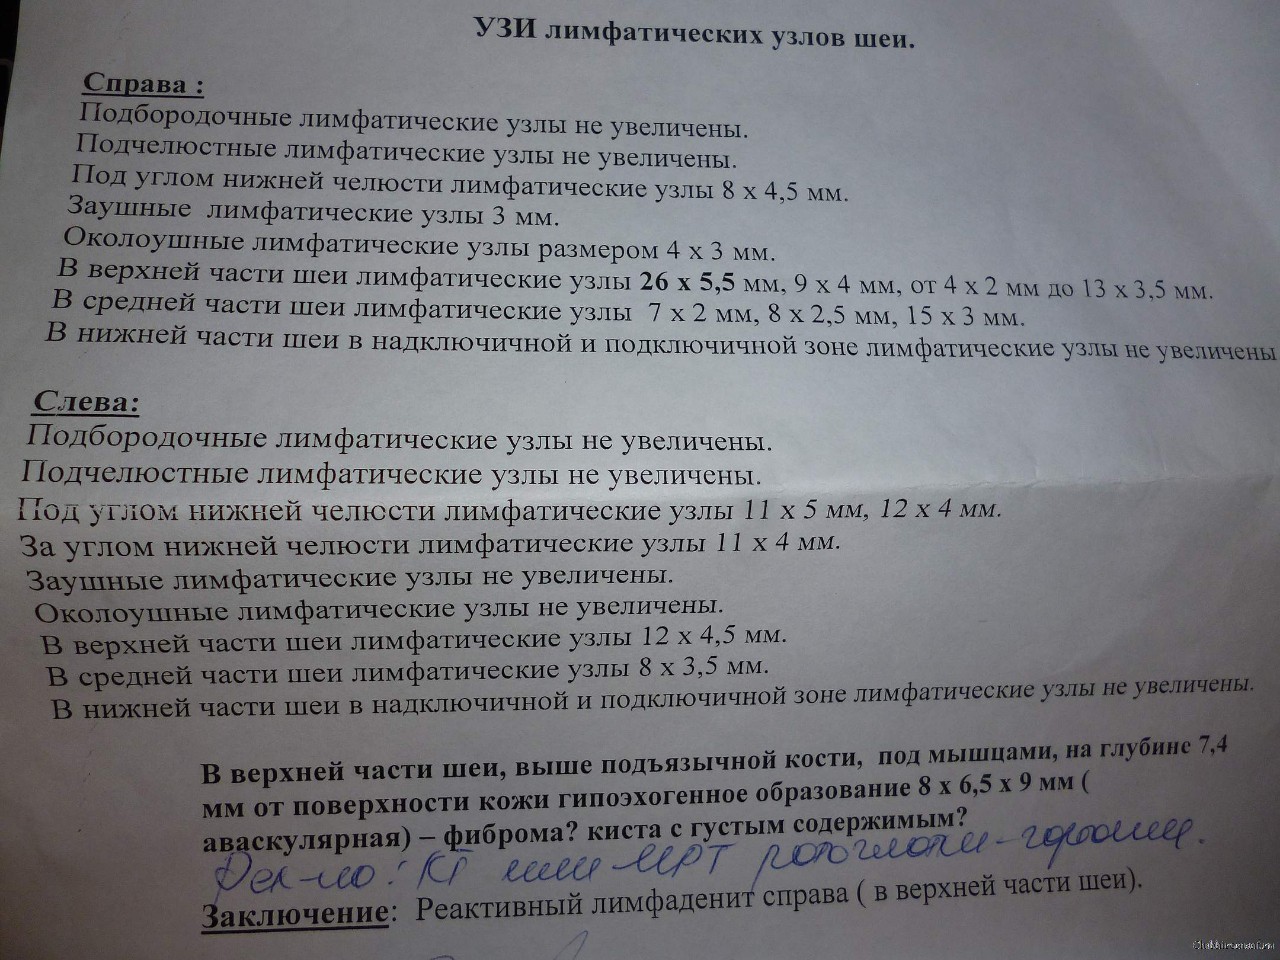

УЗИ лимфоузлов при лимфоме Ходжкина

Раздел: Образы вокруг